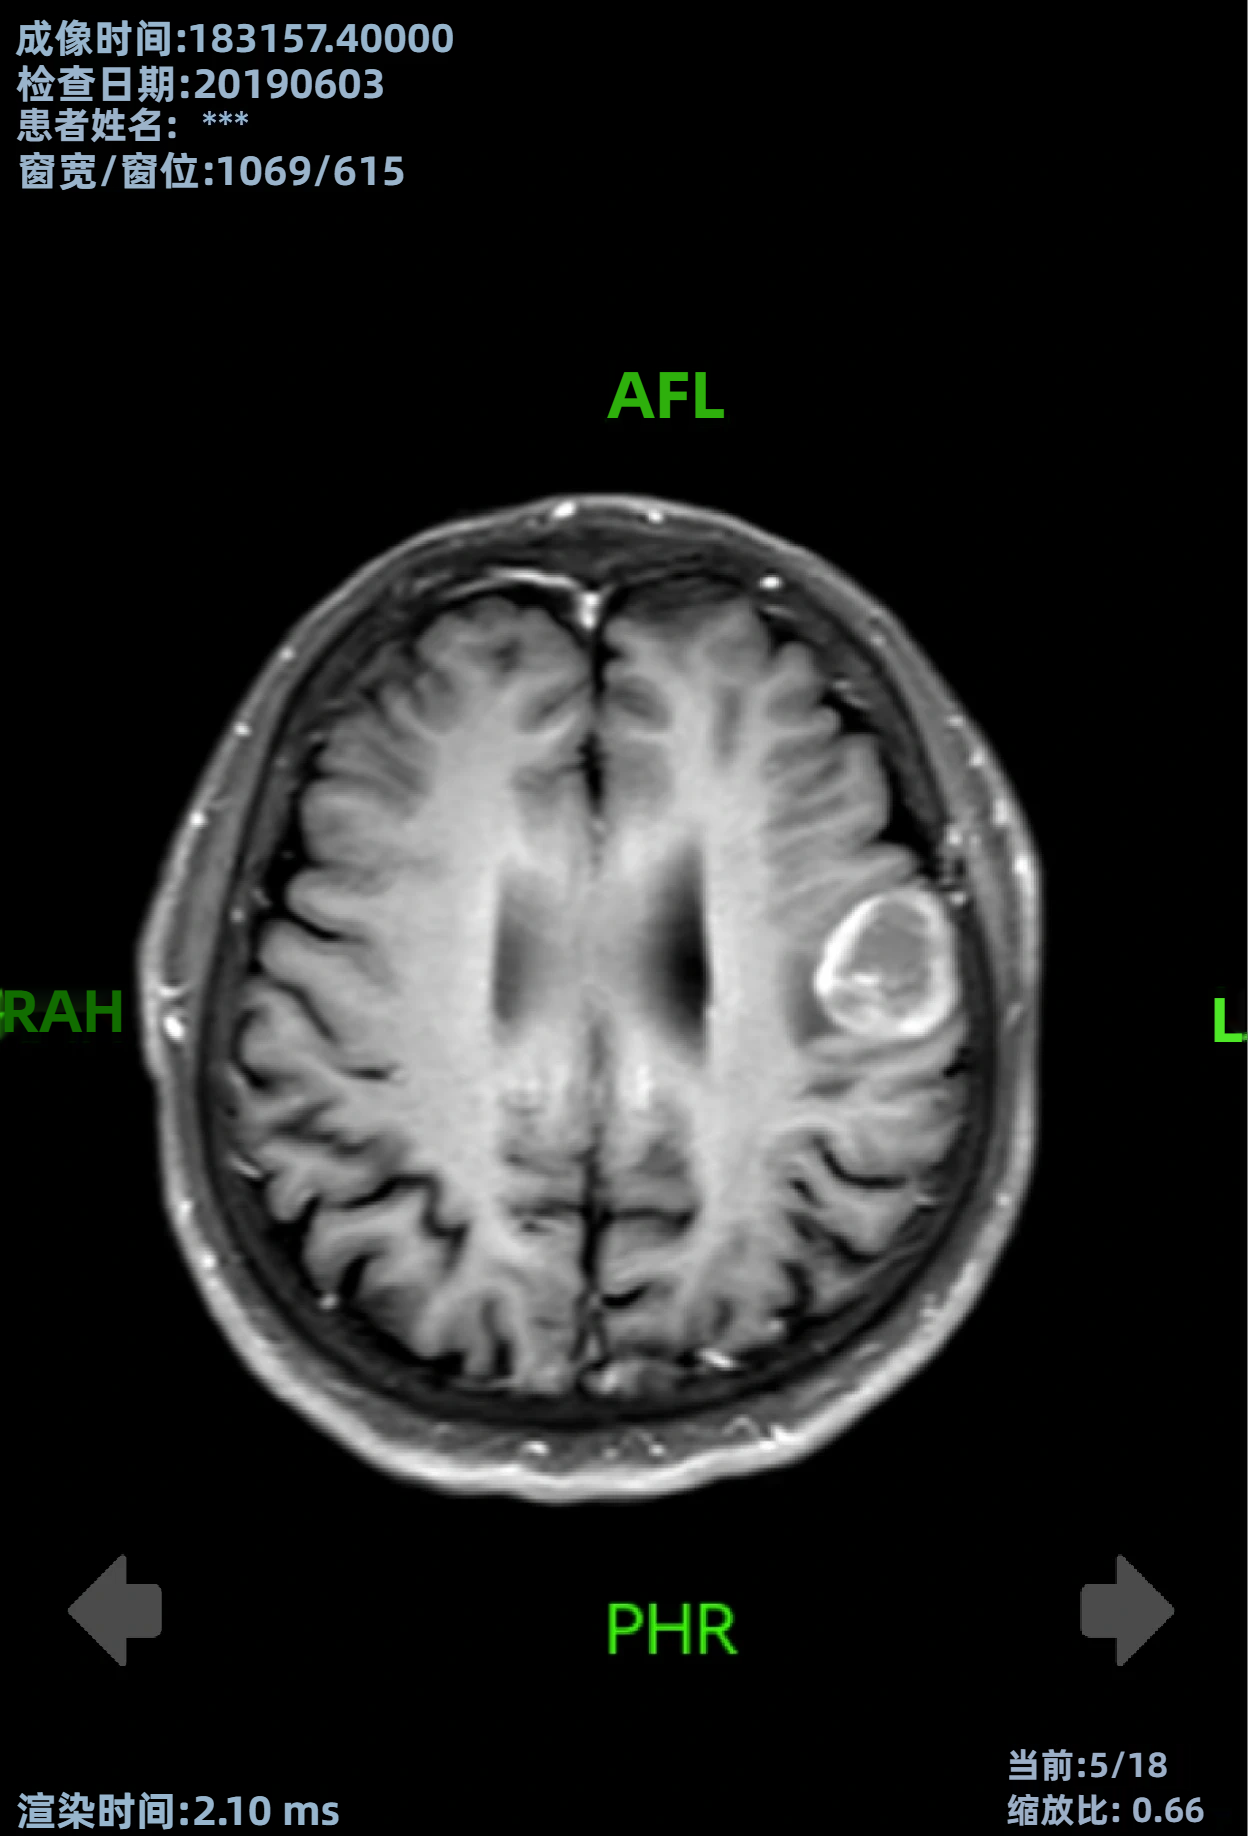

- 2026 ASCO GU | 叶定伟教授团队:放射性配体疗法治疗中国经治mCRPC获积极结果,为患者带来新选择 在本次大会的壁报环节,复旦大学附属肿瘤医院叶定伟教授团队带来了一项关于放射性配体疗法在前列腺癌中应用的前沿研究:该研究首次在中国人群中评估了¹⁷⁷Lu-PSMA-617在经紫杉烷类及雄激素受体通路抑制剂治疗失败的mCRPC患者中的有效性与安全性。……